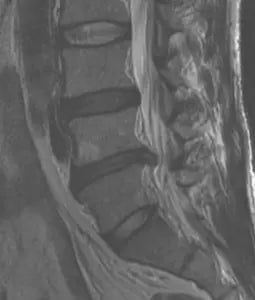

Here is an example – The patient was a 53-year-old active duty Marine Corps Master Gunnery Sergeant with a history of repetitive low back pain after a sports injury 10 years prior. He was told that he had a disk rupture with stenosis, and surgery was recommended. He underwent 1 year of physical therapy and other conservative therapies and had no improvement. His left leg started hurting, and he stated that his pain was getting worse and that it hurt to sit and lie down. An MRI was obtained and is shown below:

The comparison of the before and after MRIs are shown below. The herniation is depicted by the arrows.